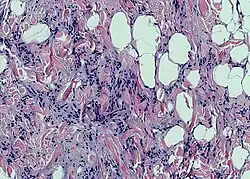

Клетки жировой ткани, накапливающие жир, называют адипоцитами. Одиночные адипоциты имеют шарообразную форму. Жировую ткань принято подразделять на белую и бурую согласно её цвету. Адипоцит белой жировой ткани содержит одну большую каплю нейтрального жира (такие адипоциты также называют унилокулярными), которая занимает центральную часть клетки и окружена тонким слоем цитоплазмы, в утолщённой части которого залегает уплощённое ядро. В цитоплазме адипоцитов содержатся в небольших количествах и другие липиды: холестерин, фосфолипиды, а также свободные жирные кислоты. Эти мелкие жировые включения особенно выражены у незрелых адипоцитов. Зрелый адипоцит имеет крупные размеры, от 50 до 150 мкм. Так как липиды вымываются ксилолом и другими растворителями, использующимися при приготовлении гистологических препаратов, унилокулярные адипоциты при рассмотрении с помощью светового микроскопа выглядят пустыми[3].

Рыхлая волокнистая соединительная ткань образует прослойки, которые делят жировую ткань на дольки разного размера и формы. В дольках адипоциты близко прилегают друг к другу, однако в жировой ткани также присутствуют клетки так называемой стромальной васкулярной фракции: преадипоциты, фибробласты, клетки эндотелия сосудов и ряд иммунных клеток, такие как макрофаги жировой ткани[1]. На клетки стромальной васкулярной фракции приходится около половины всех клеток жировой ткани[4]. Жировые клетки разделяются тонкими коллагеновыми волокнами, ориентированными во всех направлениях, а также оплетены ретикулярными волокнами[4]. Группы адипоцитов или отдельные дольки тесно охватываются кровеносными и лимфатическими капиллярами[5].